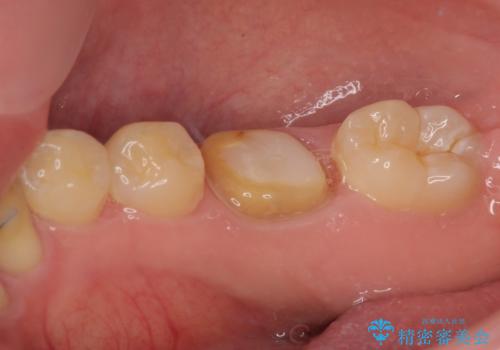

拡大鏡視野下にて、銀歯を外して、虫歯を除去して、オールセラミッククラウンに適した形に削りました。

型どりはシリコーン印象材にて型どりしています。